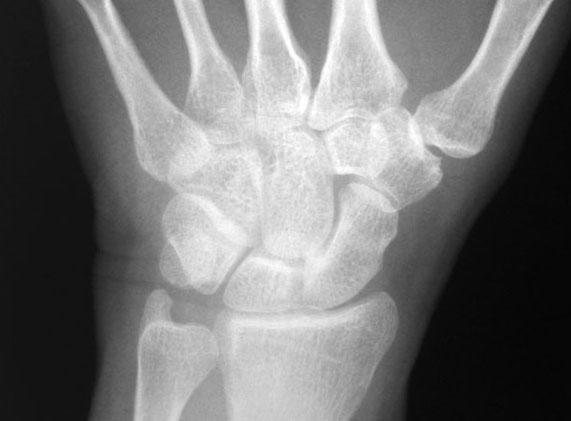

Wrist PA

The wrist is a synovial joint. The distal radius articulates with the scaphoid, lunate and triquetrum. The head of ulna is separated from the carpal bones by a fibrocartilaginous disc which articulates with the carpal bones